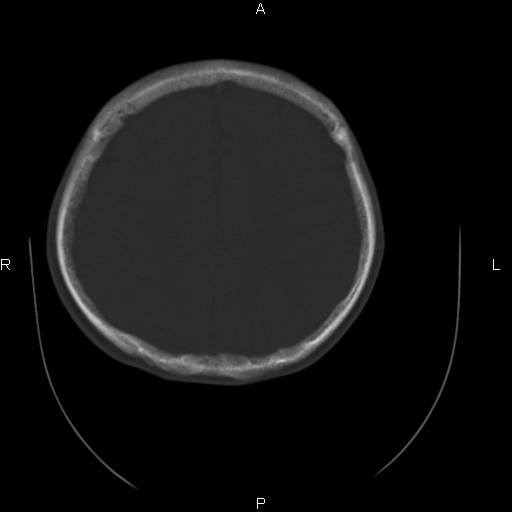

标题: CT27115:大家看一看,这孩子的颅骨表现? [打印本页]

标题: CT27115:大家看一看,这孩子的颅骨表现?

两名中学生打架,脑质内未见异常,未上传。

两例——颅骨结构正常,未见明显骨折征象。

感觉第2个颅缝密度高,额顶部板障有点厚,正常变异?地中海贫血?